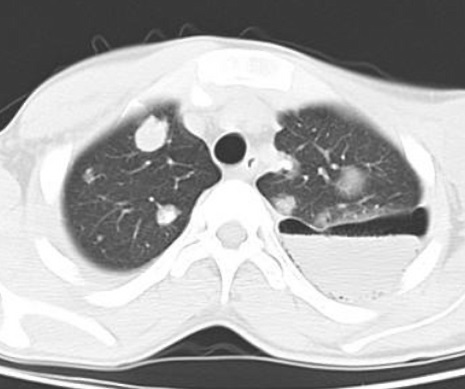

La TDM : Sur les coupe TDM fenetre

parenchymateuse , la pneumothorax est très facilement

identifié et ne devrait de poser aucune difficulté de

diagnostic. Lorsqu'une maladie bulleuse est présente un

pneumothorax loculé ce qui peut avoir aussi une apparence

similaire.

Image

radiologique cliche de face PA d'une pneumothorax du

poumon droit avec aspect de collabe legere du poumon

droit avec de zone peripherique pulmonaire n'a pas

de trame de parenchyme du pomon droit . Il est un

peut de difficile de interpreter et observer

la limite du plevre visceral pulmonaire |

Aspect radiologique de même

cas avec image de collabe du poumon droit , le

mediastin devie vers à gauche . On peut en s'observe

la limite hyperdense de la plevre visceral du poumon

droit tres nette et facilement . Image radiologique

TDM en coupe axial fenetre parenchymateuse |